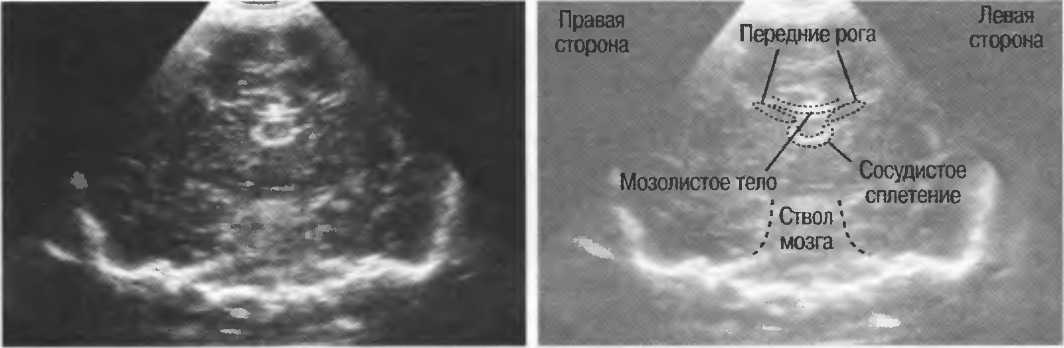

3. Ультразвуковые исследования в педиатрии. Для детей необходим датчик с частотой 5 МГц с глубиной фокусировки на 5-7 см. При исследовании мозга новорожденного используется секторный датчик с частотой 7,5 МГц с глубиной фокусировки на 4-5 см (этот датчик также используется для исследования яичек и структур шеи у взрослых).